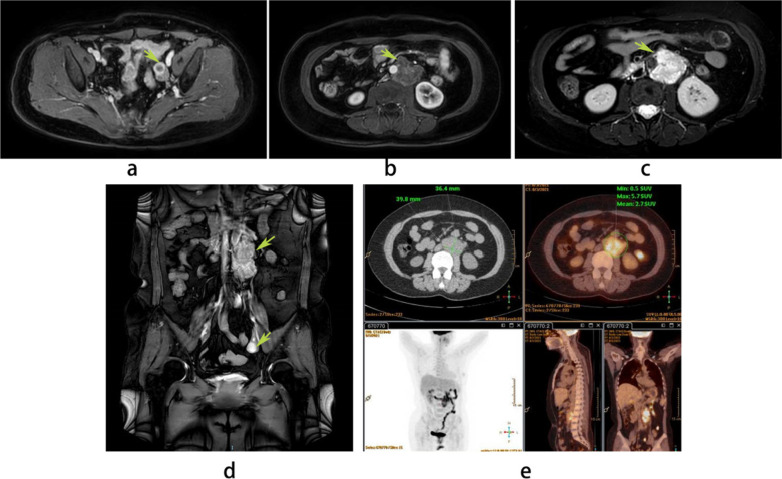

Three months ago, the patient attended the gastrointestinal outpatient department of our hospital with progressive aggravation of low back pain for more than one month. The serum CA125 was abnormally elevated (5280.20 U/ml, normal: 0–35 U/ml), HE4 was 86.0 pmol/L, carbohydrate antigen 199 and carcinoembryonic antigen levels were normal. Serum female hormones (anti Mullerian hormone, AMH: < 0.02 ng/ml; estradiol, E2: < 15 pg/ml; progestin, P:0.72 ng/ml; follicle-stimulating hormone, FSH: 27.31 mIU/ml; luteinizing hormone, LH: 8.03 mIU/ml) results suggested her postmenopausal status. Her gastroenteroscopy results showed no abnormality. Simultaneously, abdominal and pelvic enhanced magnetic resonance imaging (MRI) suggested that the left ovary was cystic and solid (Fig. 1a), and fluid or blood accumulation was considered. An irregular retroperitoneal mass at the lower margin of the first to the third lumbar spine measured approximately 75 × 42 × 37 mm3, which was considered to be a retroperitoneal malignant lymph node (Fig. 1b–d). After a multidisciplinary team (MDT) discussion by gastroenterologists, oncologists, radiologists, and gynecological oncologists, the patient was admitted to the gynecological department. Additionally, positron emission tomography and computed tomography (PET-CT) showed that the lesion was located on the left side of the retroperitoneal abdominal aorta, measuring about 70 × 40 × 36 mm3 in size with increased metabolic activity and unclear borders, with a high probability of being a malignant lymph node (Fig. 1e).

Fig. 1.

Findings on imaging of the patient. An MRI revealed that the left ovary was cystic and solid (a), and the irregular retroperitoneal mass at the lower margin of the first to the third lumbar spine measured approximately 75 × 42 × 37 mm3 (b–d). A PET-CT scan demonstrated that the lesion was on the left side of the retroperitoneal abdominal aorta about 70 × 40 × 36 mm3 in size with increased metabolic activity and unclear borders (e)